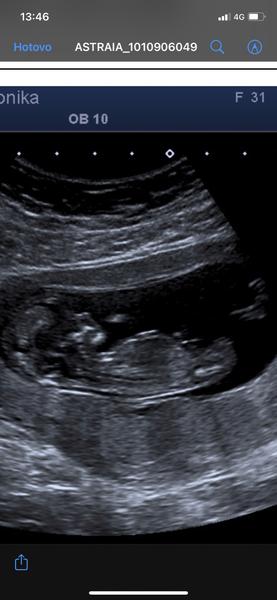

@klokanka31 Jj, snad bude všechno v pořádku. První screening na jedničku, malý tam celou dobu dělalo kotrmelce a hrozně mě to uklidnilo 🙂